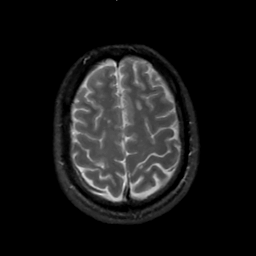

MR Study #2, February 17, 1991 -- Slice #40

[Home][Help][Clinical][Tour 1][Tour 2] Slice 40